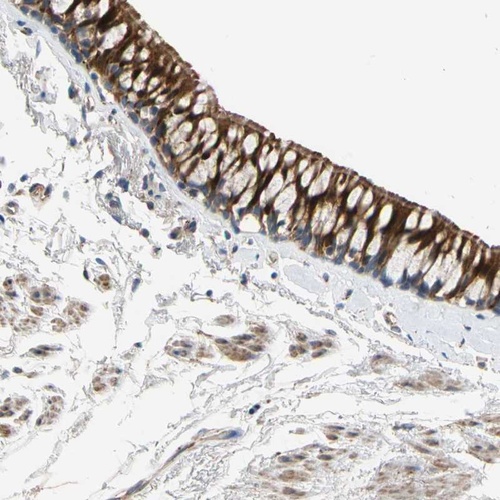

Immunohistochemical staining of human bronchus shows strong cytoplasmic positivity in respiratory epithelial cells.